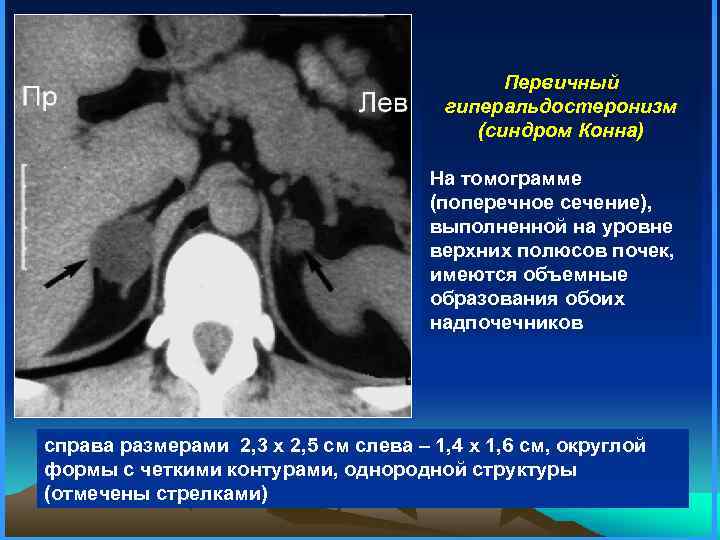

Первичный гиперальдостеронизм (синдром Конна) На томограмме (поперечное сечение), выполненной на уровне верхних полюсов почек, имеются объемные образования обоих надпочечников справа размерами 2, 3 х 2, 5 см слева – 1, 4 х 1, 6 см, округлой формы с четкими контурами, однородной структуры (отмечены стрелками)

Первичный гиперальдостеронизм (синдром Конна) На томограмме (поперечное сечение), выполненной на уровне верхних полюсов почек, имеются объемные образования обоих надпочечников справа размерами 2, 3 х 2, 5 см слева – 1, 4 х 1, 6 см, округлой формы с четкими контурами, однородной структуры (отмечены стрелками)